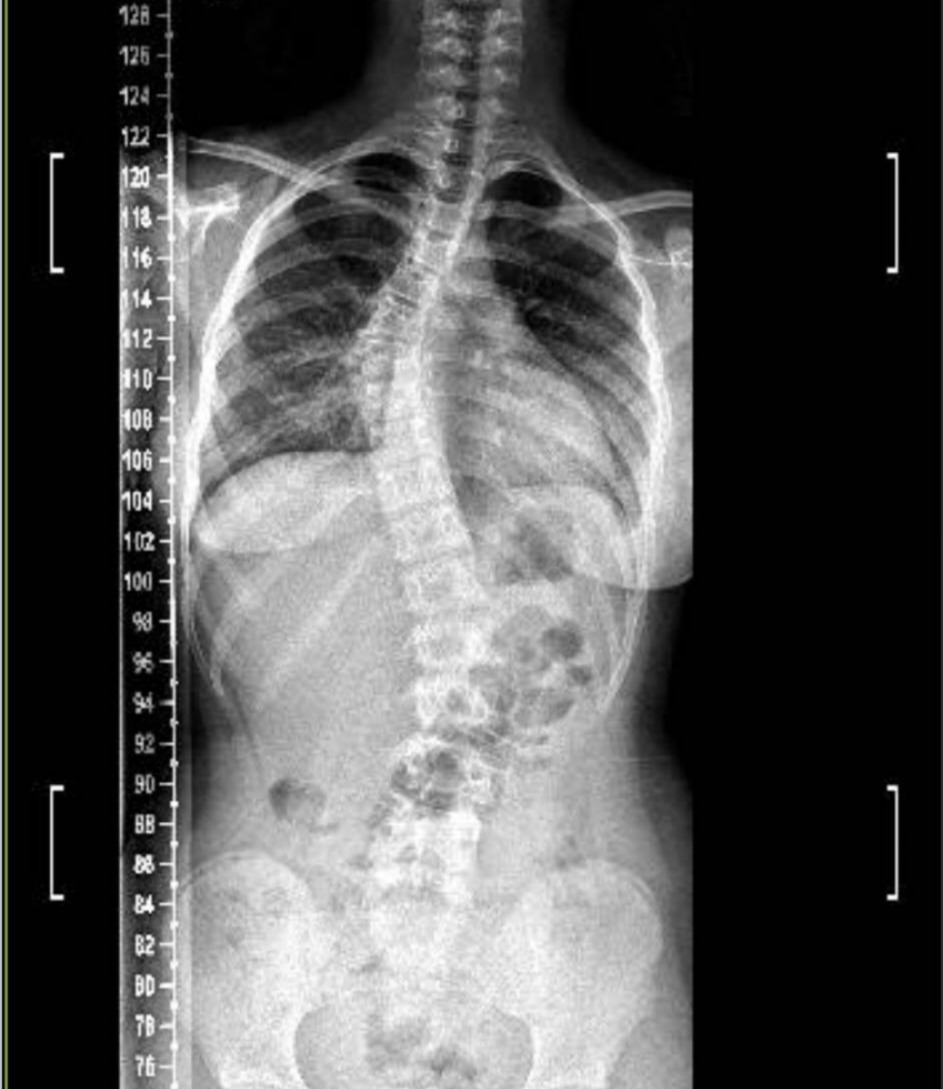

La pequeña Nicole Ibarra, de 12 años, recientemente fue diagnosticada con escoliosis y los médicos le han recetado el uso de un corsé ortopédico y la obra social no lo cubre. Por lo cual se lanzó una campaña solidaria para recaudar el monto de 1.400.000 pesos, que es el costo del corsé.

En una visita a Medios El Independiente, Rosa y Andrea, mamá y tía de la pequeña, comentaron que la pequeña comenzó el año pasado con dolores y nauseas por lo cual realizaron la consulta médica “y me dicen que tenía una leve desviación en la columna, pero en estos últimos meses avanzó muchísimo, por lo cual necesita utilizar un corset ortopédico las 24 horas del día. Ella siente mucho dolor y necesitamos conseguirlo urgente”.